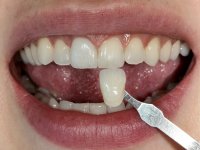

A pre-print was performed to make a crown in dual-cured resin. After a cross-section with a turbine, the infiltrated crown was removed with a microluxador. The dental stump was re-prepared to better define the shape and location of the cervical margin. It was necessary to place composite resin on the buccal surface of the provisional crown to improve its esthetics. The impression was made using a double-mix technique with two-viscosity, quick-setting silicones. In the laboratory, a crown with a ceramic-coated Zr infrastructure was made. After placing it in the mouth, we verified that the crown showed a greater translucency than the symmetrical one, not fulfilling our aesthetic goals. The ceramist had the opportunity to observe the situation in the clinic, collecting records for later rectification. The new crown was placed in the mouth and approved by the patient. The final cementation was done with resin-reinforced glass ionomer cement.